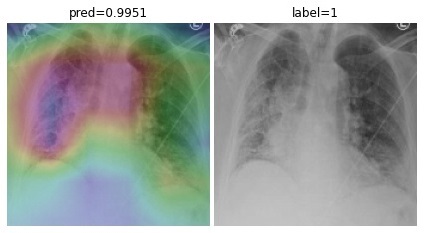

To overcome the aforementioned issues and force the model’s attention to the correct regions of interest (ROIs), we introduce the COVID-CXNet. Our model is initialized with the pretrained weights from CheXNet. A dataset of 3,628 images, 3,200 normal CXRs and 428 COVID-19 CXRs, are divided into 80% as training-set and 20% as test-set. Batch size is set to 16, rather than 32 in previous models, regarding memory constraints. Grad-CAMs of the COVID-CXNet for random images are plotted in Fig. 15.

Figure 15: Grad-CAM visualization of the proposed model over sample cases

More Grad-CAMs are available in Appendix A. Heatmaps are more accurate than previous models, while an accuracy of 99.04% and an f-score of 0.96 are achieved. Table 3 is the confusion matrix of the proposed model.